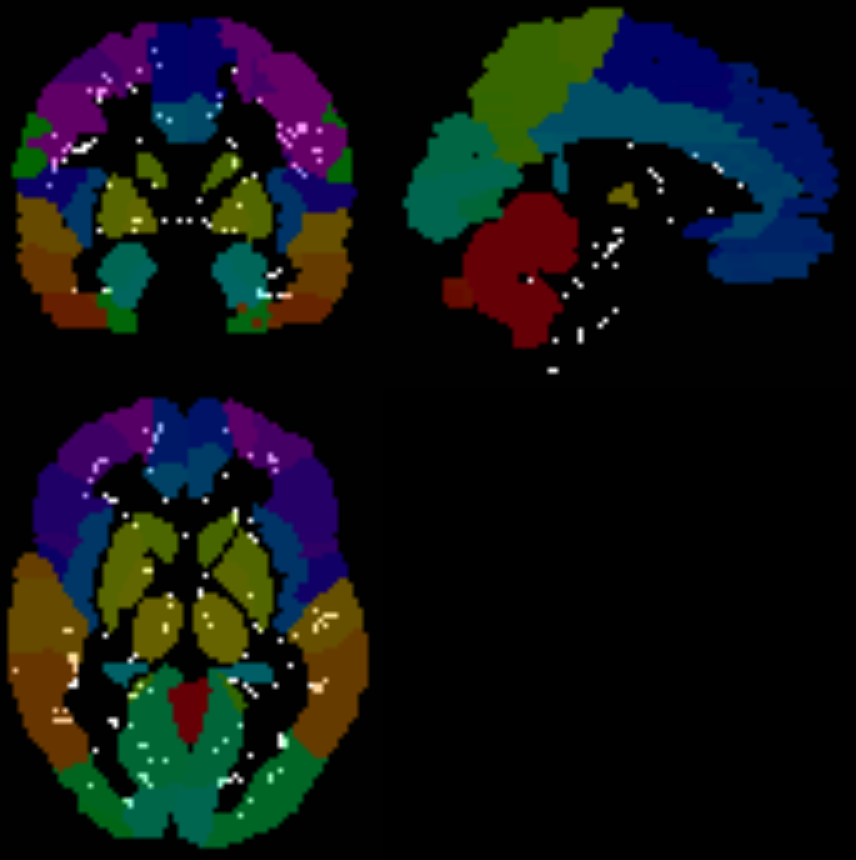

On the contrary, some limited samples exhibit a higher number of voxels showing differences after the contrast analysis. This is clearly an undesirable behaviour taking into account the outcome with larger sample sizes. Taking the OLIN center as an example, we can observe the voxels that have been identified as different after the permutation test using SPM in Figure 11, superimposed on the image provided by the AAL atlas. These voxels, located near the edges of different regions, can be attributed to registration artifacts, which can arise from anatomical variations among subjects or discrepancies between the atlas-defined regions and the detected regions during image registration. Also, some differences are concentrated in the brain stem, as it is shown in the same figure.

Refer to caption

(a)

(b)

Figure 11: SPM t-map in ASC vs HC comparison of OLIN center, compared to the AAL atlas (a), and compared to the GM map (b).